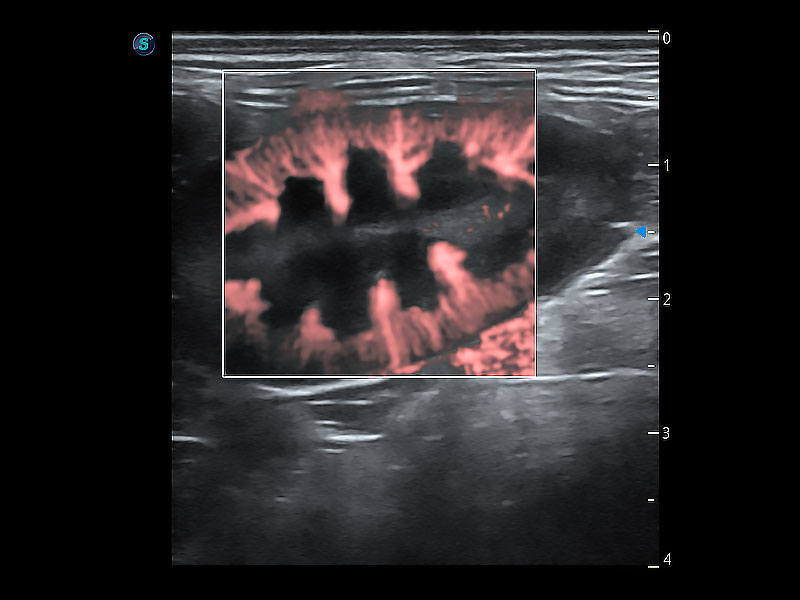

优异的基础图像

ProPet 80 全新的动物超声智能软件和丰富的探头群,为动物医生提供了高清晰度和精细分辨率的图像,无论在宠物、马科、畜牧还是实验室动物等应用中都可以轻松应对,为您的日常工作带来满意的体验。

(犬)肾脏显微血流

• Micro F 显微血流成像

极大提升超低速微细血流的检出能力,同时更精准地滤除软组织和超声信号,为兽用医生提供以往无法通过常规血流获得的疾病诊断信息。

• Bright Flow 立体血流成像

在传统二维血流成像的基础上,呈现血流的立体感,具有动感的生命力之美。即便是微小的血管也能轻松应对,提高了血流的视觉敏感性。